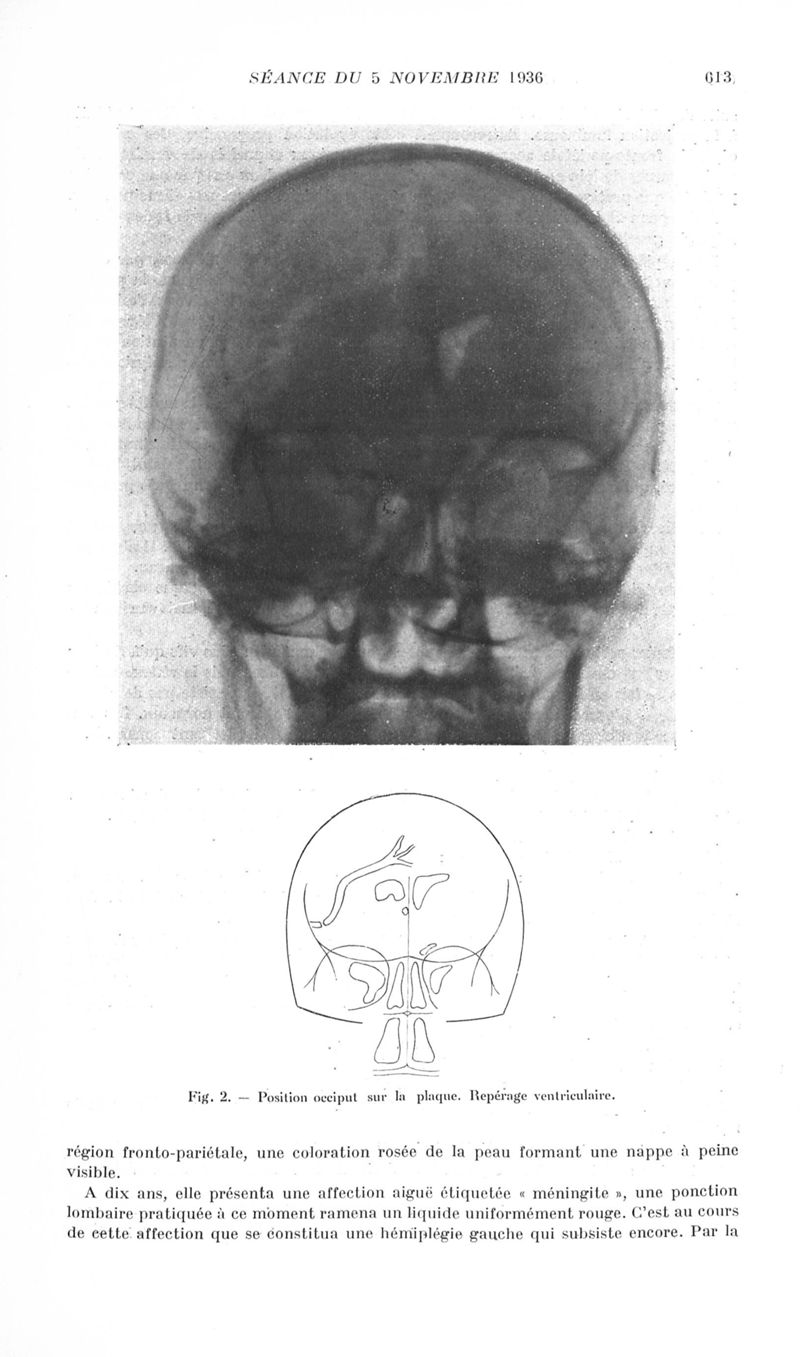

Revue neurologique

1936, vol 2. - Paris : Masson , 1936.